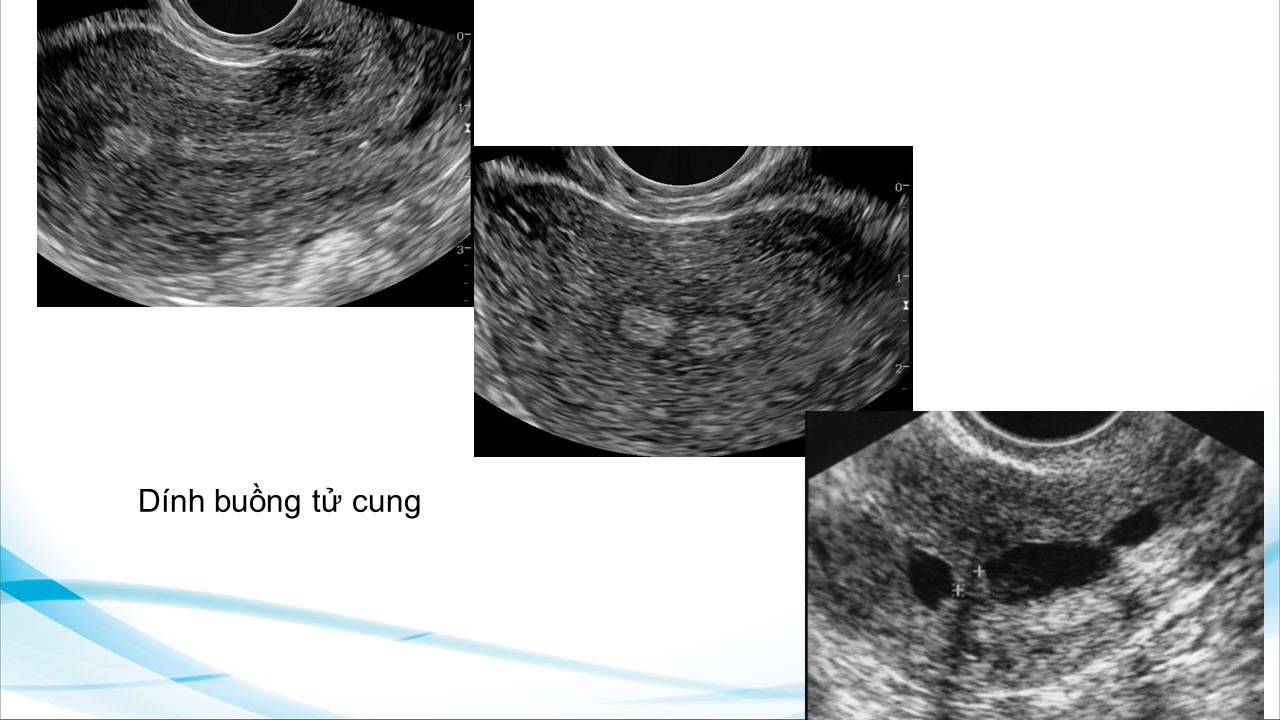

Siêu âm theo dõi trong bơm tinh trùng vào buồng tử cung và thụ tình trong ống nghiệm